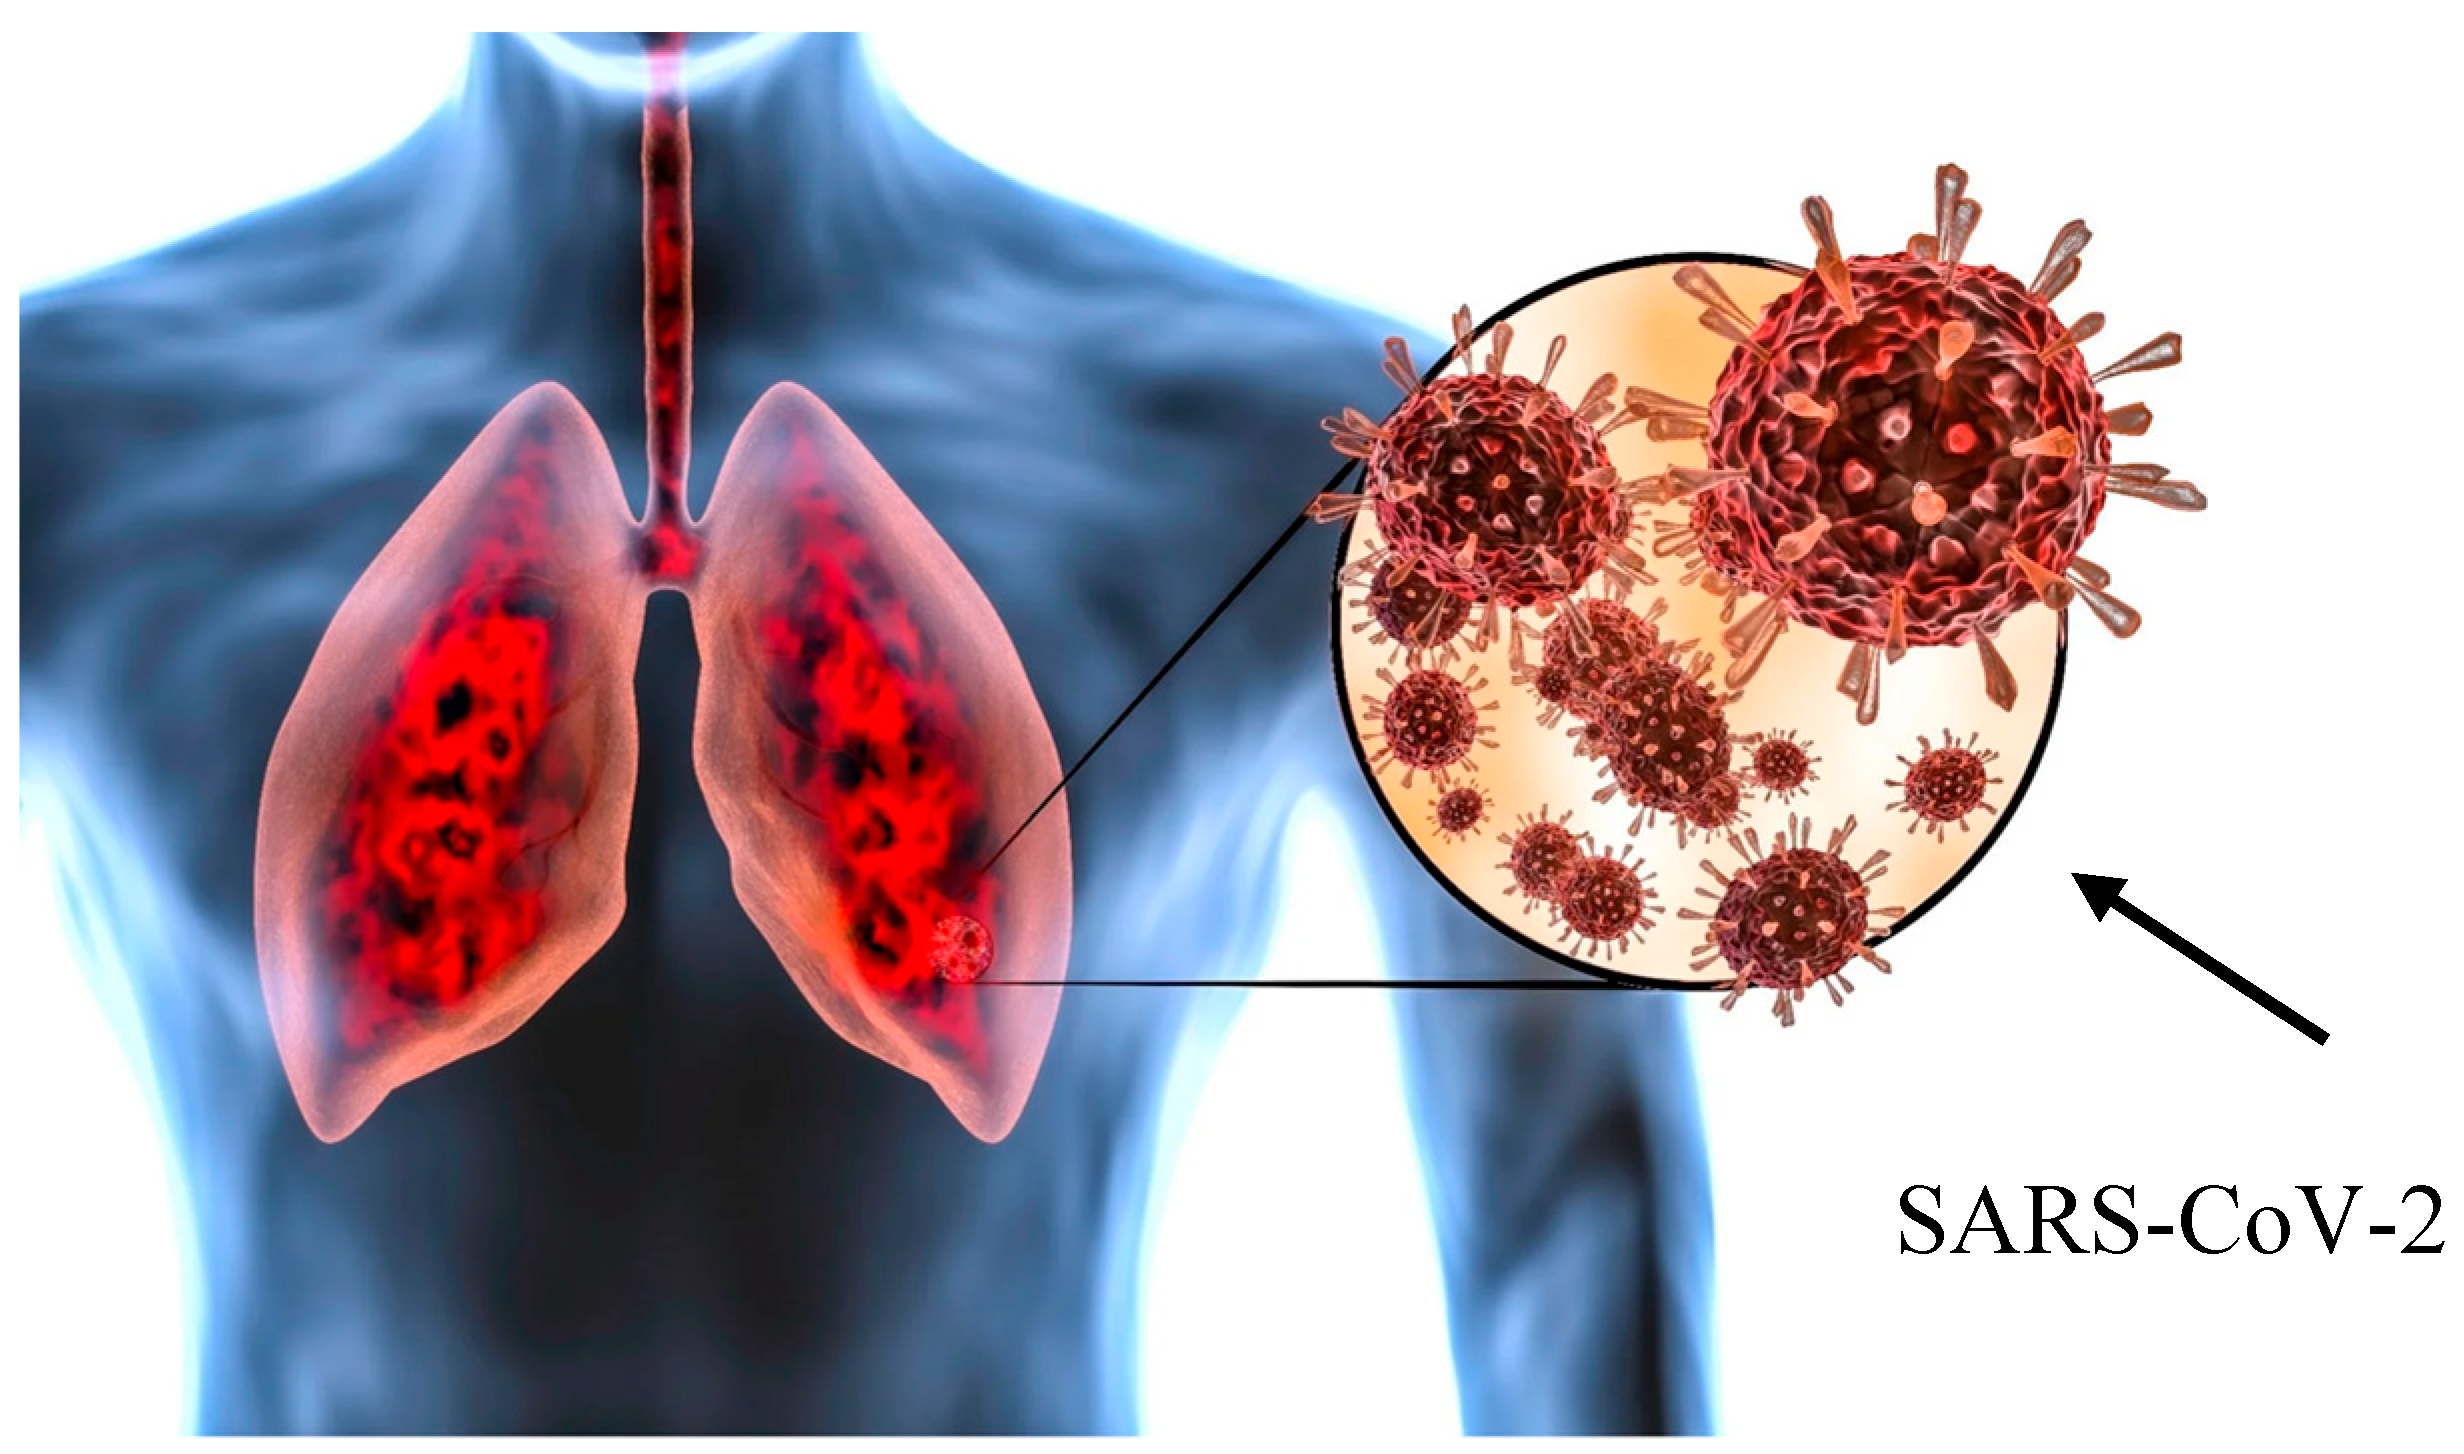

Cluster 2 (“acute/subacute injury”) was characterized by a great variety of lung injury patterns, including diffuse alveolar damage, organizing pneumonia, and fibrosing nonspecific interstitial pneumonia. The histopathology included diffuse thickening of the alveolar interstitium by myofibroblast proliferation and dense fibrosis. Remnant alveolar spaces showed type II pneumocyte hyperplasia (Figure 5), which expressed phosphorylated signal transducer and activator of transcription 3 (pSTAT3) and Ki67. Nodular lymphocytic infiltrates were noted in the perivascular and interstitial spaces.

Figure 5. Hyperplastic alveolar epithelial type II cells (AECII). Magnification: H&E ×100.